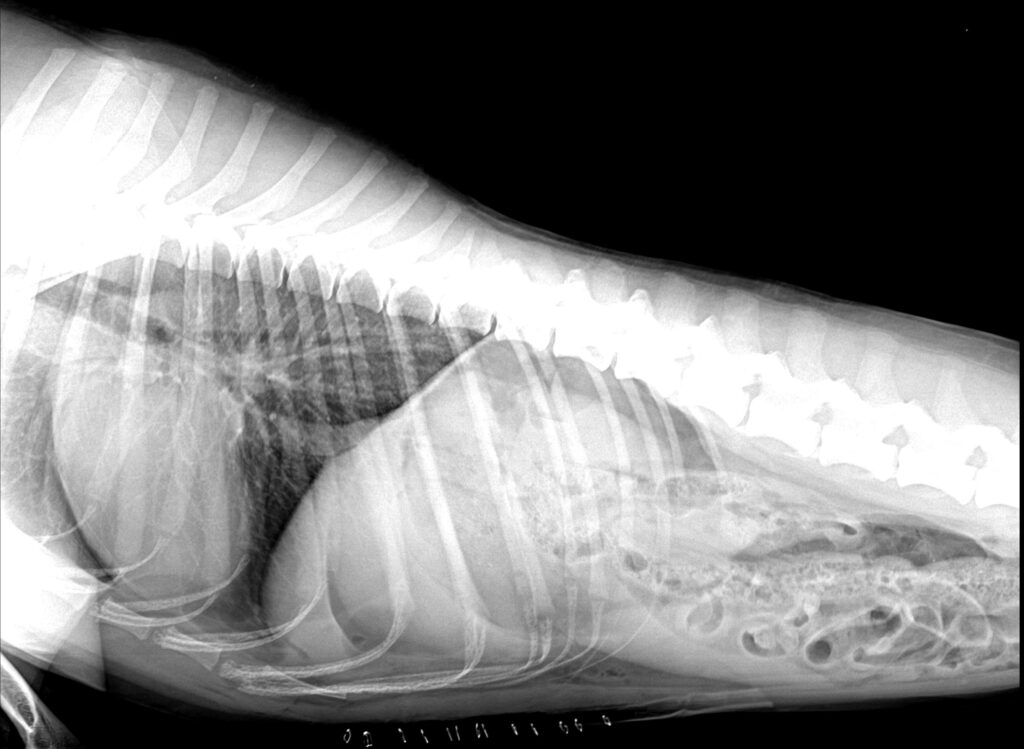

수술 후 방사선 사진 / 출처: 미래동물의료센터